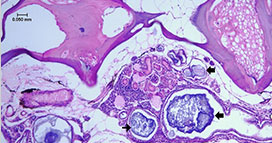

6、吉姆薩染色

吉姆薩染液由天青�,伊紅組成。嗜酸性顆粒為堿性蛋白質(zhì)�,與酸性染料伊紅結(jié)合,染成粉紅色����,稱為嗜酸性物質(zhì);細(xì)胞核蛋白和淋巴細(xì)胞胞漿為酸性�����,與堿性染料美藍(lán)或天青結(jié)合��,染成紫藍(lán)色����,稱為嗜堿性物質(zhì);

中性顆粒呈等電狀態(tài)與伊紅和美藍(lán)均可結(jié)合�����,染淡紫色,稱為中性物質(zhì)���。